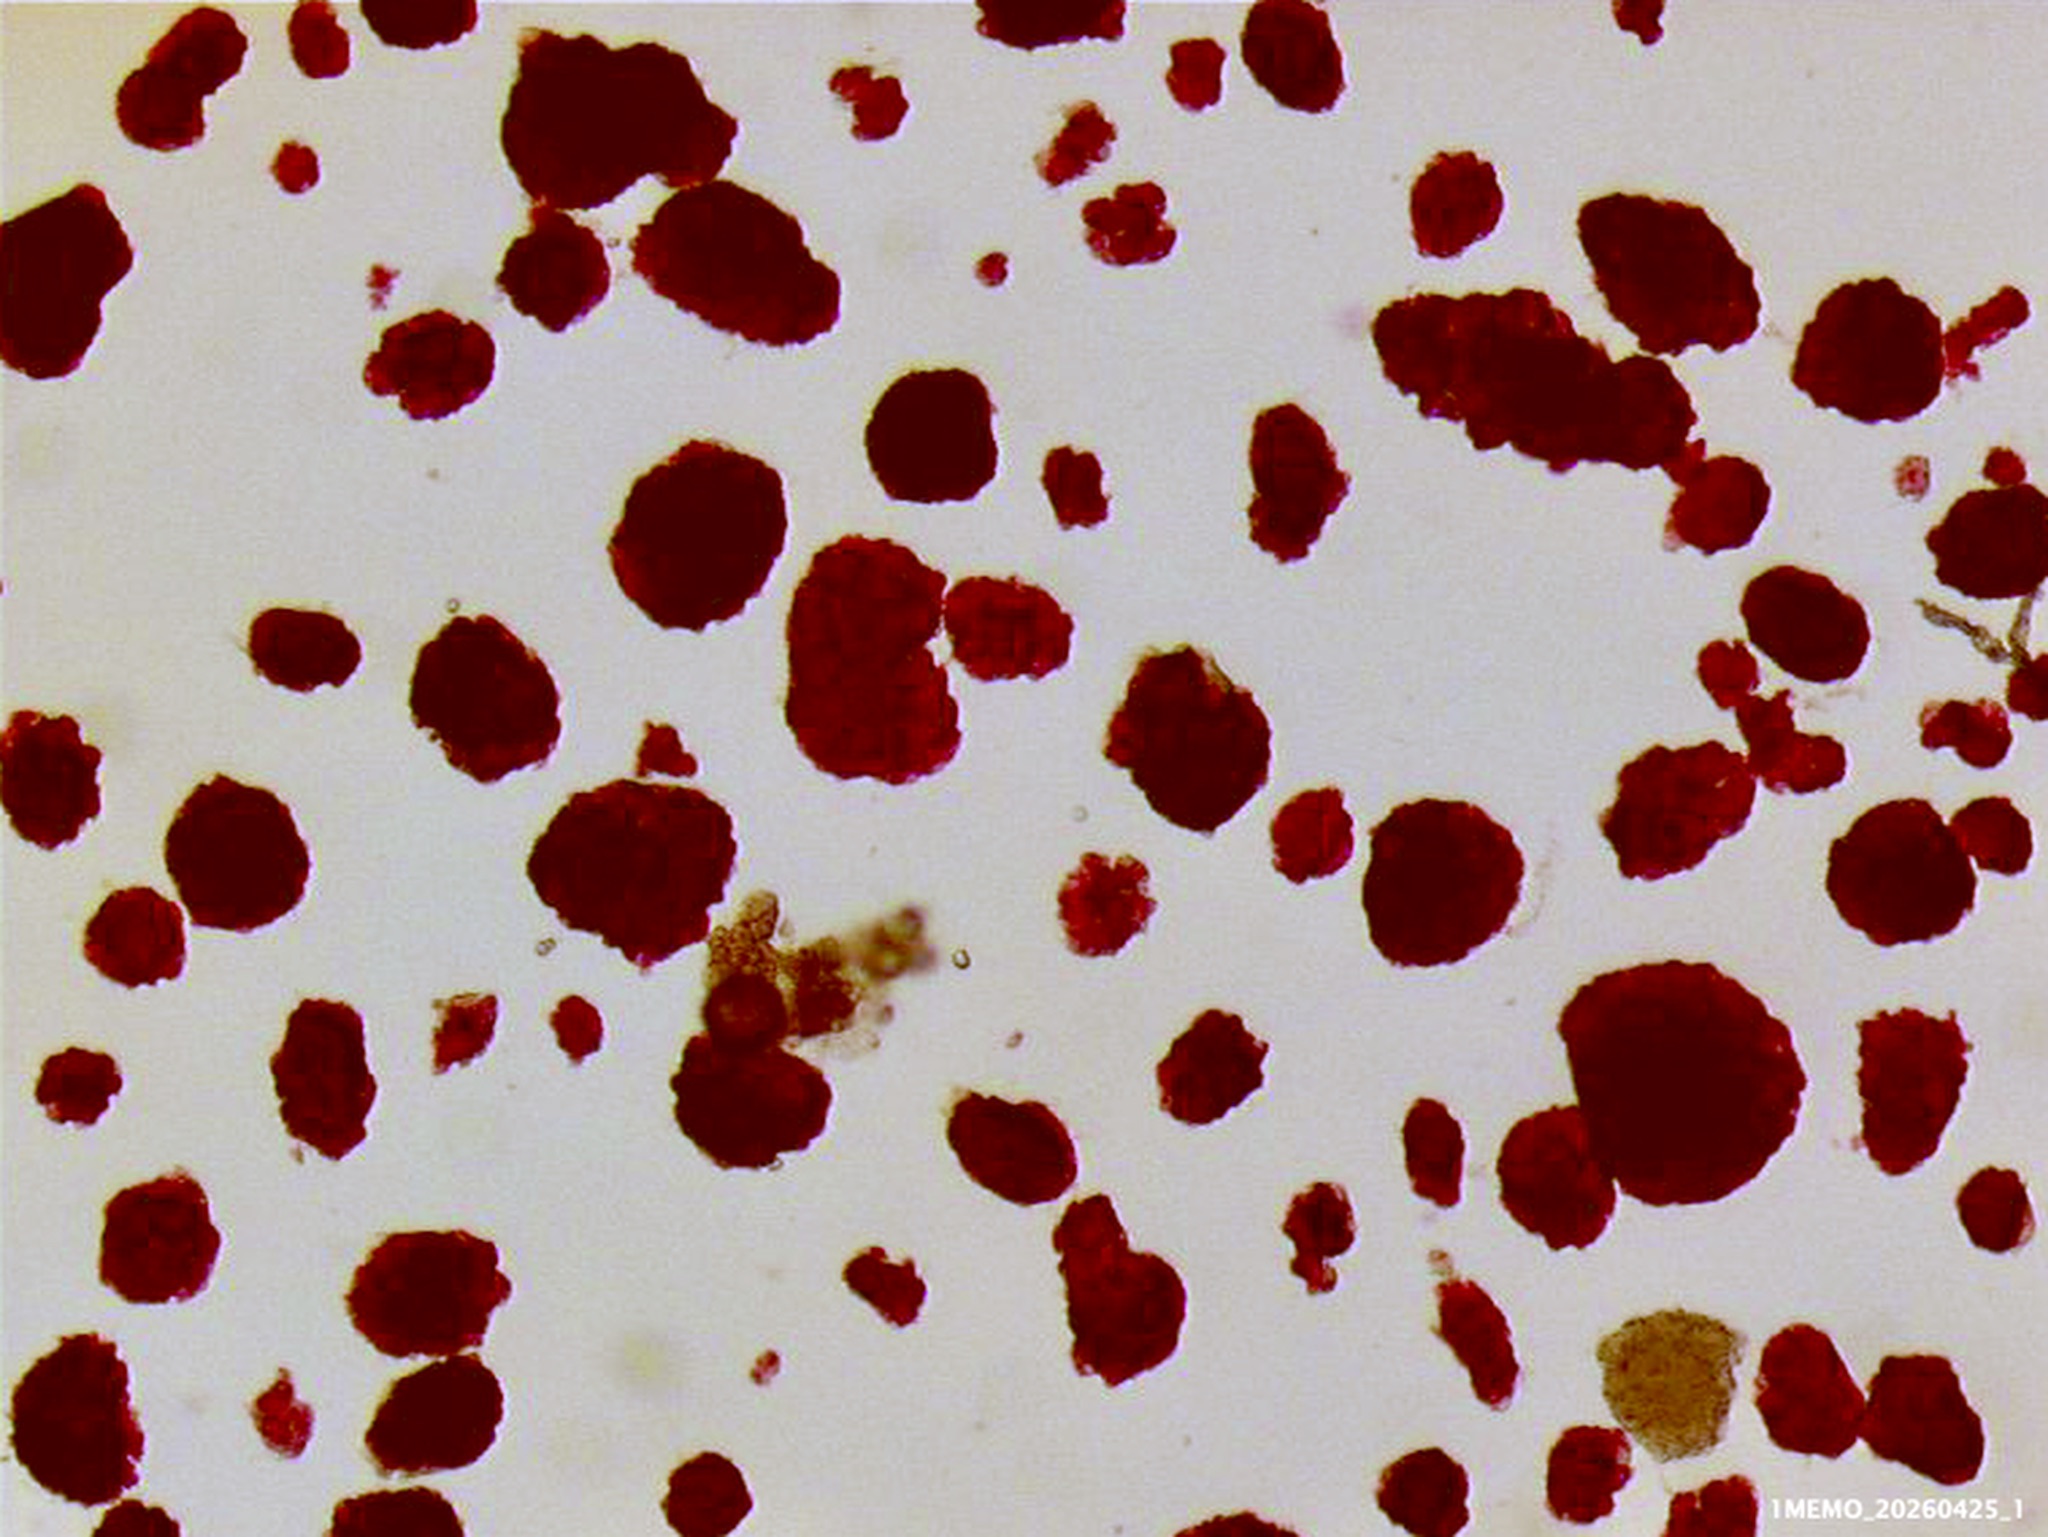

I photographed the isolated cynomolgus islets both before culture (stained red with dithizone), and after one day culture (not stained, in the petri dishes used for culture).

Cynomolgus monkey islets purified in Iodixanol-UWS • 1MEMO_20260425_1 • Michel van der Burg • Miracles•Media • TakeNode 893e099a-13b2-42cd-a3e9-17bcbe14d3d9 • Islets not cultured, identified by staining red with dithizone, after overnight preservation in cold UWS (due to logistics).

After purification of these islets in our Iodixanol-UWS density gradient solution , virtually pure islets were obtained (a mean 94% purity) , with virtually no loss of islets (a mean 90 % recovery).